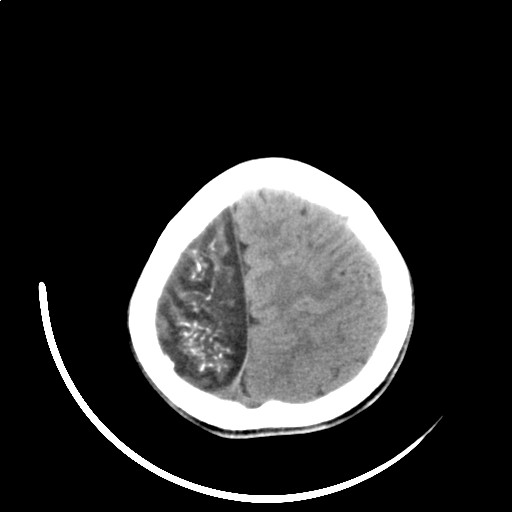

标题: PED3416:F,12Y,智力下降,学习成绩差,8个月时发过高烧。

右侧大脑发育不良伴动静脉畸形。

右侧半球萎缩,软化,多量脑回样钙化,考虑颅面血管瘤病,建议dsa检查

右侧半球萎缩,软化,多量脑回样钙化,同侧颅盖板障增宽,考虑颅面血管瘤病,建议dsa检查与化脓性脑膜炎后遗改变鉴别。